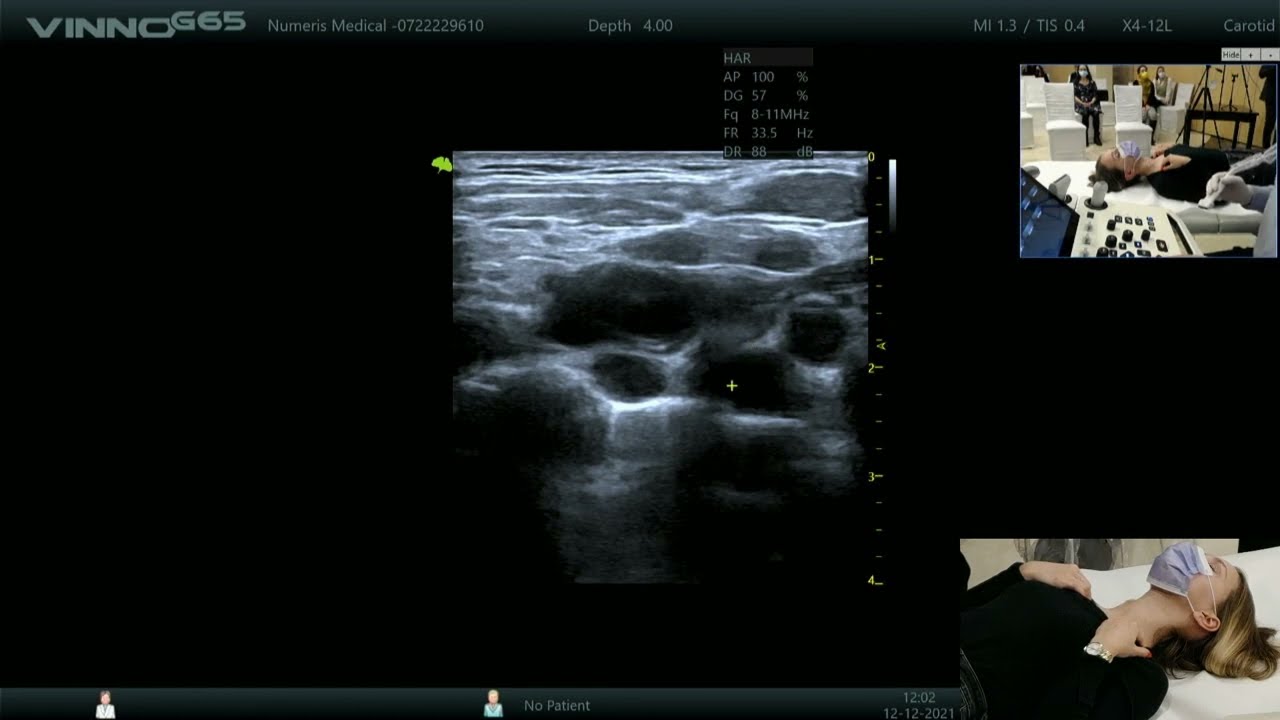

Screeningul se face prin realizarea unei ecografii abdominale, ca metodă principală de diagnostic, care are rolul de a identifica prezenta anevrismului aortic abdominal la persoanele cu risc de boală. Ecografia abdominală va permite măsurarea cu acuratețe orice dilatare a aortei abdominale.